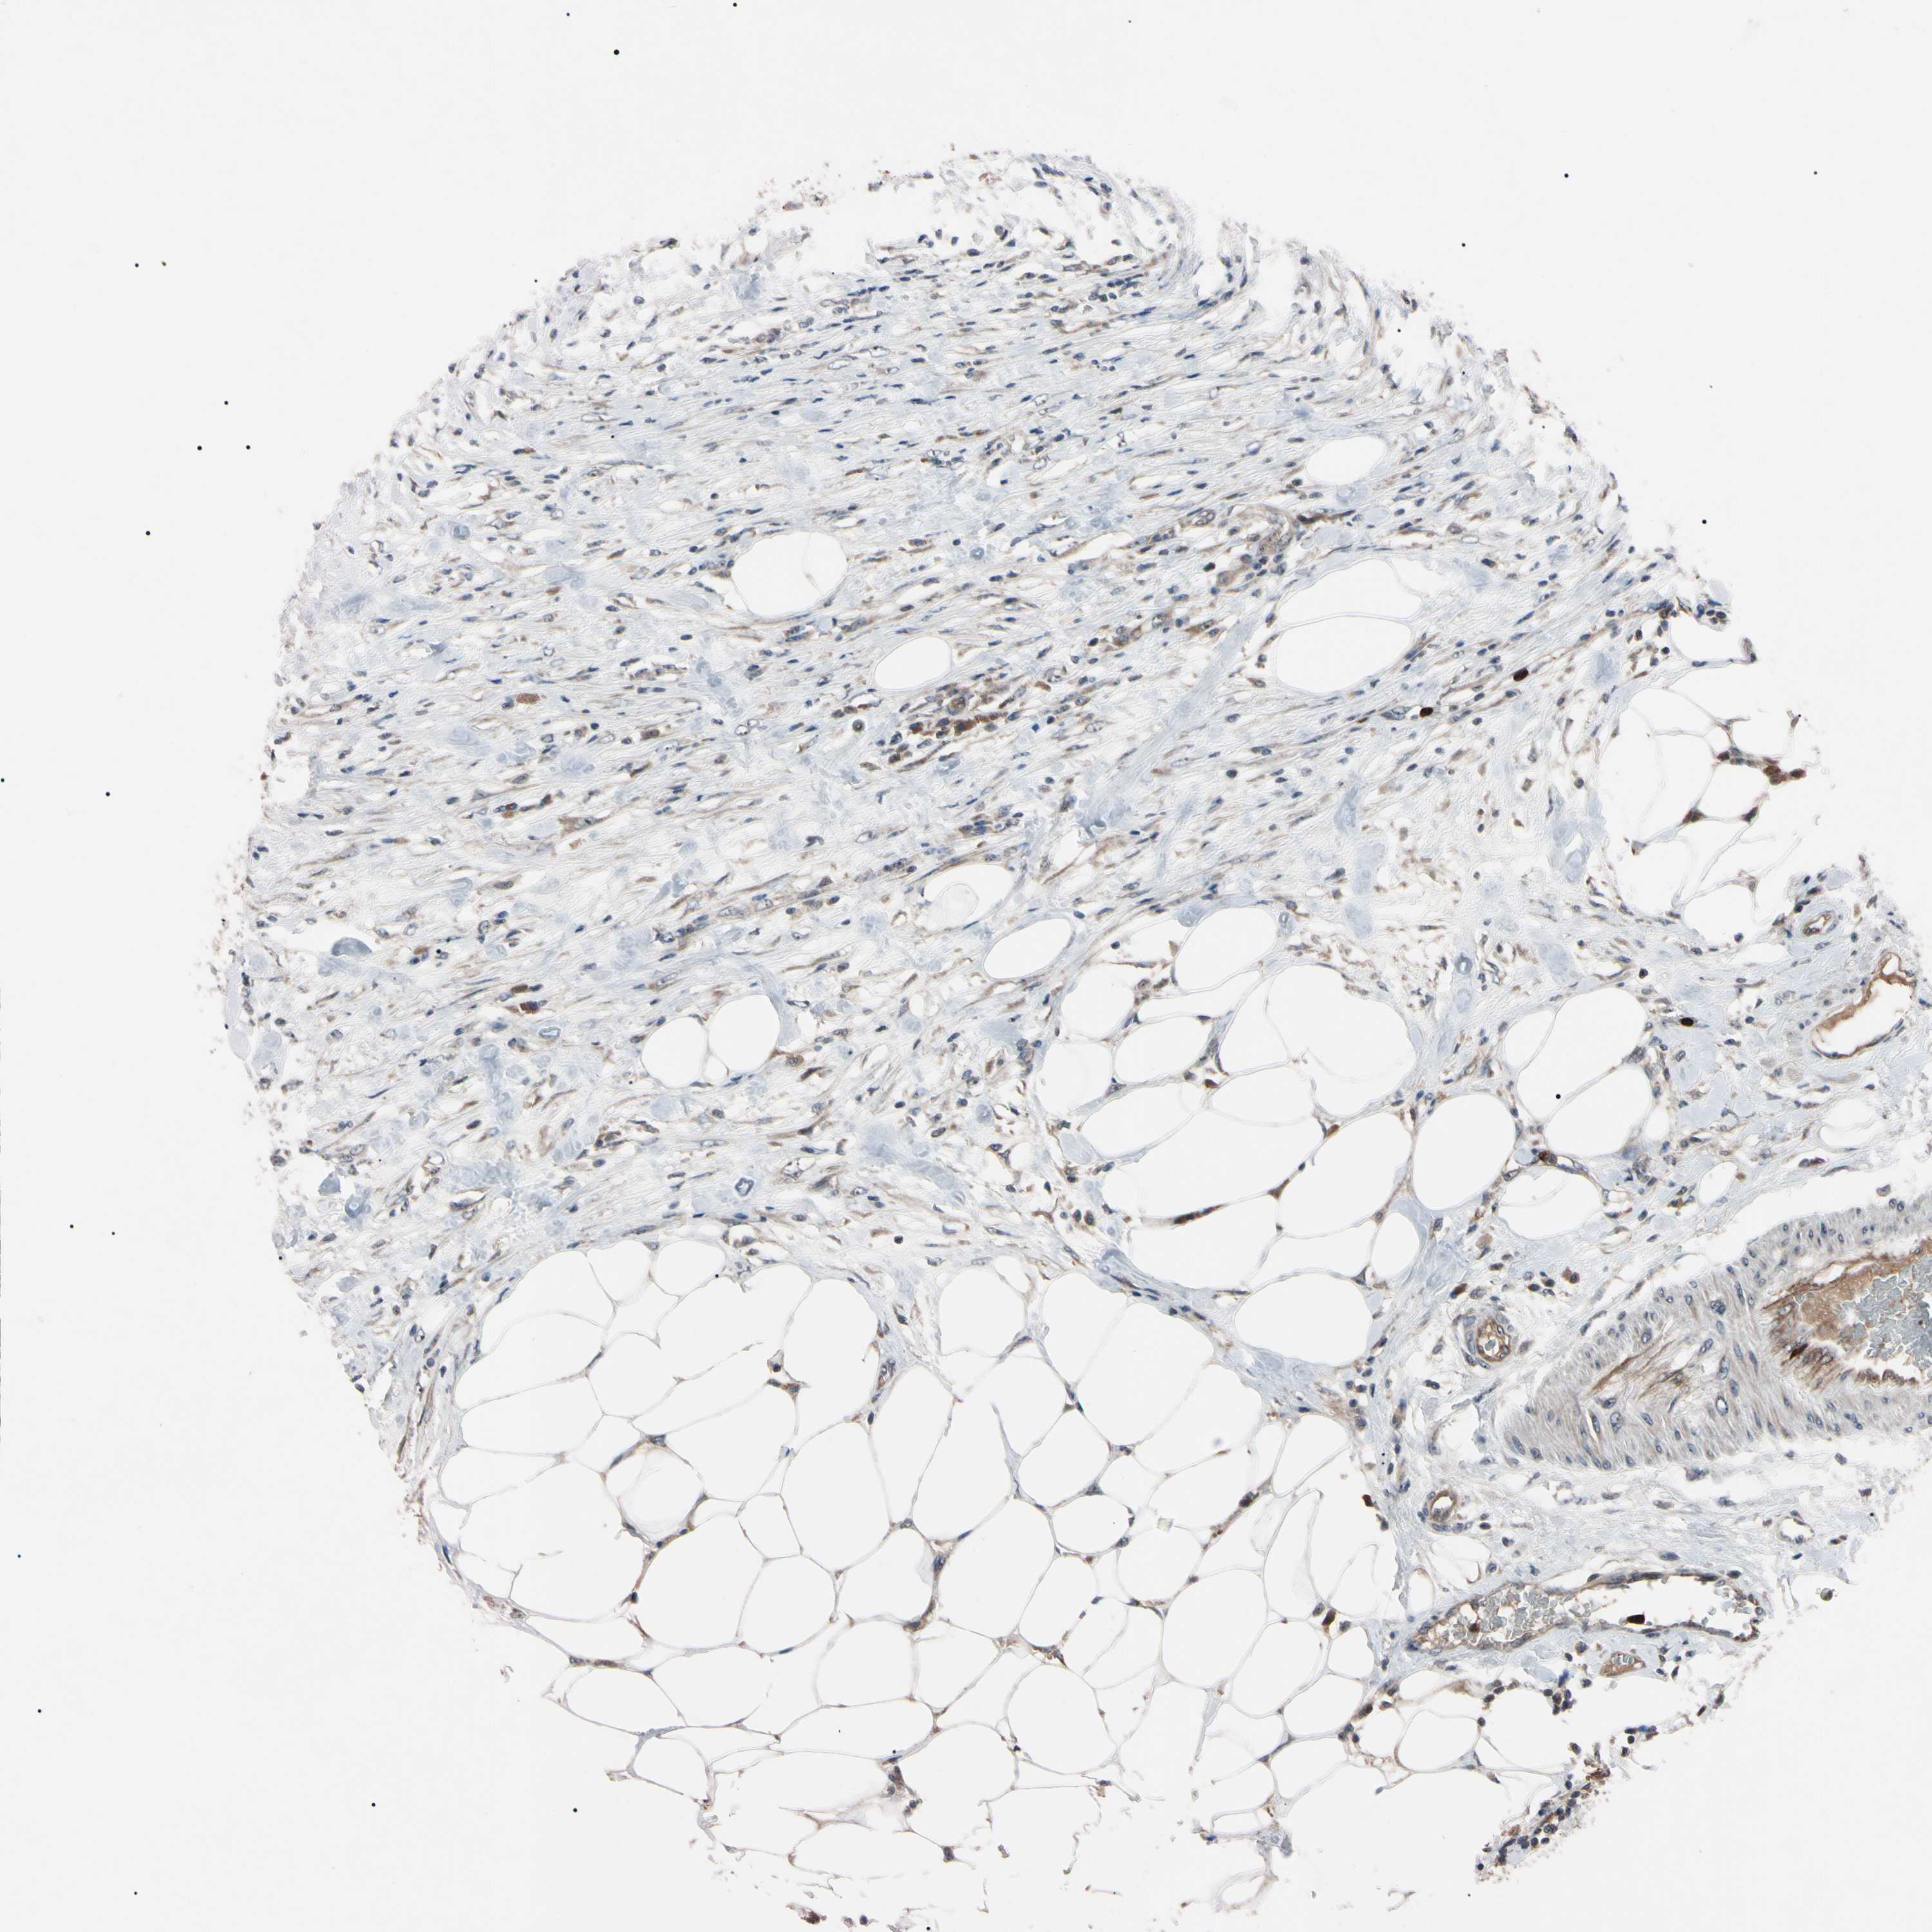

UROTHELIAL CANCER - Protein expressioni

A mouse-over function shows sample information and annotation data. Click on an image to view it in a full screen mode. Samples can be filtered based on level of antibody staining by selecting one or several of the following categories: high, medium, low and not detected. The assay and annotation is described here.

Note that samples used for immunohistochemistry by the Human Protein Atlas do not correspond to samples in the TCGA dataset.

Antibody stainingi

Antibody staining in the annotated cell types in the current human tissue is reported as not detected, low, medium, or high, based on conventional immunohistochemistry profiling in selected tissues. This score is based on the combination of the staining intensity and fraction of stained cells.

Each image is clickable and will lead to virtual microscopy that enables deeper exploration of all samples and also displays staining intensity scores, fraction scores and subcellular localization as well as patient and tissue information for each sample.

Antibody HPA008052

Antibody CAB010277

Staining

High

Medium

Low

Not detected

Intensity

Strong

Moderate

Weak

Negative

Quantity

>75%

75%-25%

<25%

None

Location

Nuclear

Cytoplasmic/membranous

Cytoplasmic/membranous,nuclear

Urothelial carcinoma, Low grade

Urothelial carcinoma, High grade